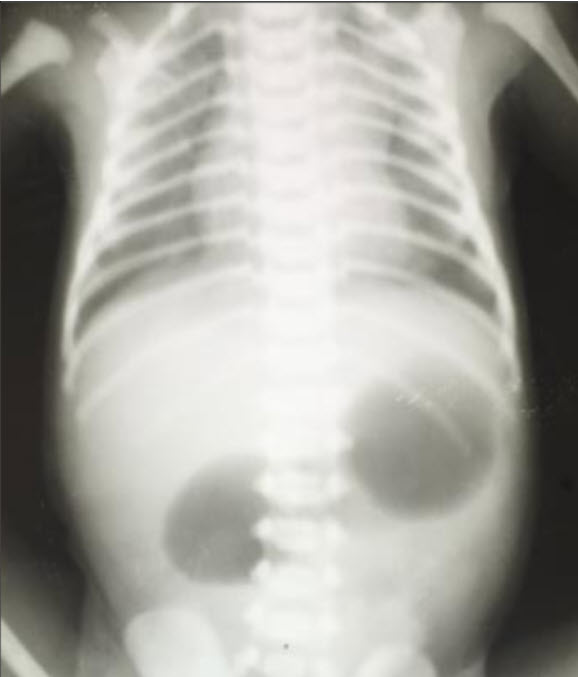

A 40-year-old woman delivers a newborn male. Her pregnancy was normal except that she noted decreased fetal movement compared to her previous pregnancies. She declined an amniocentesis offered by her obstetrician. Physical examination of the newborn reveals an infant with facial features suggestive of Down Syndrome. The infant then has bilious vomiting. An x-ray film showing the kidneys, ureters, and bladder (KUB) is performed, which shows a "double bubble" sign.

Which of the following is the most likely cause of the abdominal signs and symptoms?

A. Duodenal atresia